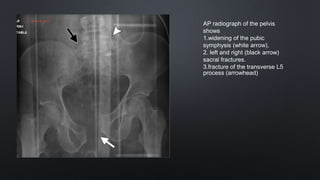

AP radiograph of the pelvis

shows

1.widening of the pubic

symphysis (white arrow),

2. left and right (black arrow)

sacral fractures.

3.fracture of the transverse L5

process (arrowhead)